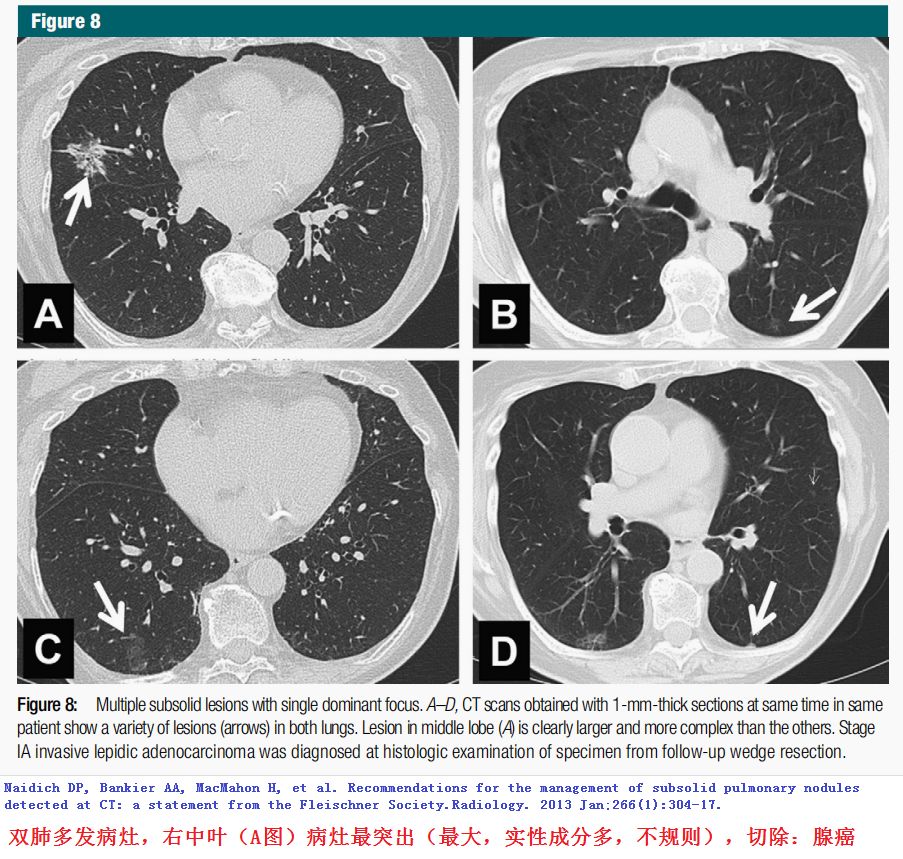

下面这些病灶良恶难确定,随访是重点!

随访后病灶增大,手术切除!

(图片点击均可放大)

1.Naidich DP, Bankier AA, MacMahon H, et al. Recommendations for the management of subsolid pulmonary nodules detected at CT: a statement from the Fleischner Society.Radiology. 2013 Jan;266(1):304-17.